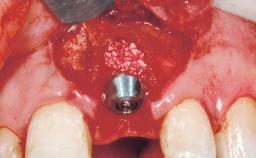

Immediate Placement of an Implant in a Maxillary Right Central Incisor Site

A 30-year-old female patient was referred to the office for the treatment of tooth 11. Her chief concern at the initial visit was to inquire, “Why is my tooth pink?” Upon clinical examination, it was determined that tooth 11 had a previous history of trauma and that the clinical crown had become noticeably pink in color as a result of internal resorption. This diagnosis was confirmed radiographically, indicating a large radiolucency involving the central and distal portions of the clinical crown. It was determined that restoration of this tooth was not possible, and that extraction was indicated. The presence of a mid-line diastema, which the patient wanted to reproduce, directed the treatment plan for tooth replacement utilizing a dental implant.

Placement Protocol Immediate implant placement

Tooth Site Maxillary incisor or canine

Socket Morphology Single-root socket

Socket Integrity Sufficient, with intact bone walls